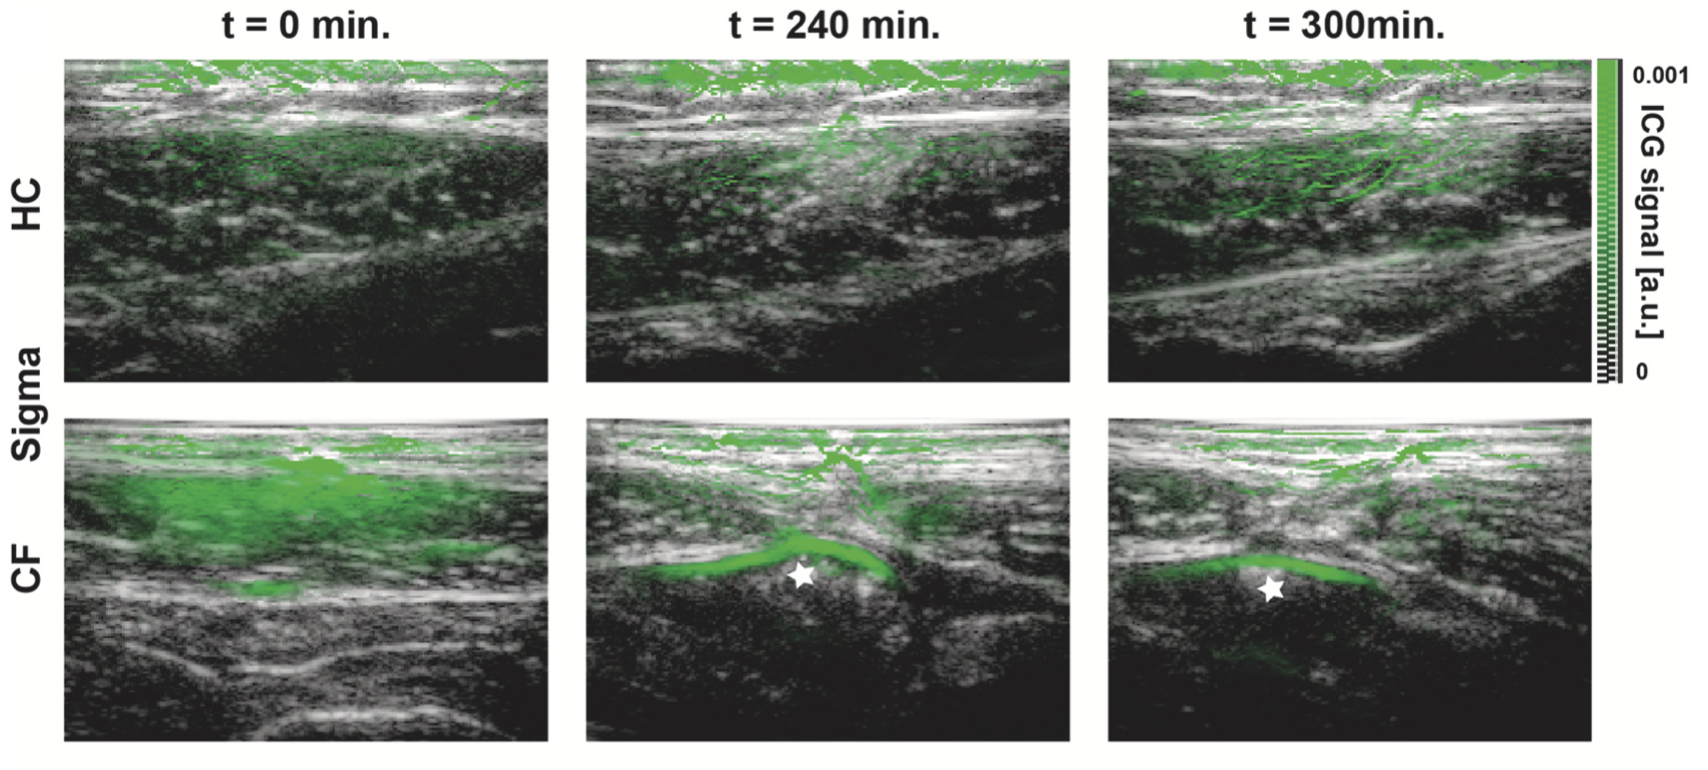

CE-MSOT bietet einen innovativen, nicht-invasiven Ansatz: Nach Einnahme des Farbstoffs Indocyaningrün (ICG)können lichtinduzierte akustische Signale genutzt werden, um den Verlauf des Farbstoffs durch den Verdauungstrakt sichtbar zu machen. Das Verfahren kombiniert Ultraschall und Optoakustik und erlaubt dadurch eine dynamische und präzise funktionelle Bildgebung.

In der Studie erhielten fünf CF-Patientinnen und -Patienten sowie vier gesunde Kontrollpersonen ein standardisiertes Frühstück mit ICG. Anschließend wurden stündlich Aufnahmen des Magens, Dünndarms und Dickdarms durchgeführt.

CF-Patienten erreichten das Signalmaximum bereits nach 120 Minuten, gesunde Personen erst nach 240 Minuten. -

Nachweis des Farbstoffs im Dickdarm nur bei CF:

Im Sigmoid konnte der Farbstoff während der Untersuchungszeit ausschließlich bei CF-Patienten detektiert werden.

Diese Befunde weisen auf eine beschleunigte intestinale Passage bei Mukoviszidose hin – möglicherweise beeinflusst durch moderne CFTR-Modulator-Therapien, die die Funktion des Chloridkanals verbessern.